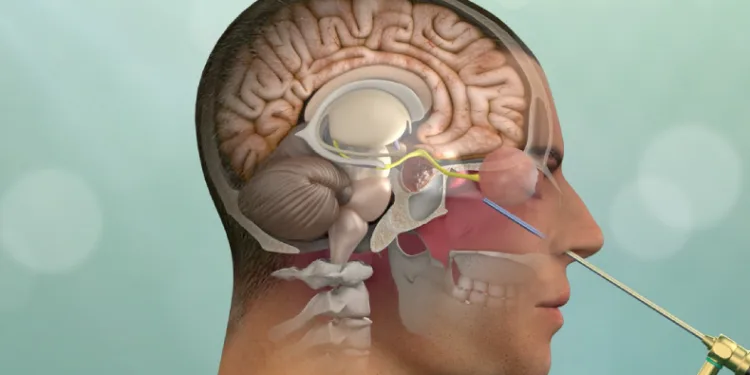

“Burun deliğinden endoskopik cerrahi ile tümör çıkarılır”

Hipofiz bezi adenomları genellikle iki görme sinirinin hemen altında, 1’e 1 santimlik bir alanda kafa tabanında yerleştiğini belirten Prof. Dr. Mahmut Akyüz, eğer görme bozukluğuna ya da hastada hormon eksikliğine veya fazlalığına neden olmuşsa, cerrahi ile tedavi edilmesi gerektiğine vurgu yaptı. Prof. Dr. Mahmut Akyüz, “Endoksopik hipofiz bezi ameliyatlarında; her iki burun deliğinden veya bir tanesinden endoskopi vasıtasıyla girilerek kafadaki birtakım anatomik boşluklar, hava boşlukları ve sinüs boşluklarından da yararlanılarak hipofiz tümörünün bulunduğu yere ulaşılır ve o bölgedeki tümör çıkarılır. Endoskopik hipofiz bezi ameliyatında kafatasının açılmamış olması ve ameliyat sonrasında herhangi bir pansumana ihtiyaç duyulmaması hastaya büyük konfor sağlar” diye konuştu.

“Tümörün tipine göre, patolojik evrelemesine, atipik olup olmamasına, agresif olup olmamasına göre bazen ameliyat sonrası radyoterapi, ilaç tedavisi de verilebilir. Ameliyat için hastanın daha önce burundan büyük bir cerrahi geçirmemiş olması gerekmektedir. Ayrıca doğal anatomik hava boşluklarının cerrahinin yapılabilmesi için yeterli olması şarttır. Bazen doğuştan var olan sinüs boşluklarının tamamen kapalı olması, ulaşılacak yol önünde bir kemik duvar olmasına neden olur. Bu durumda cerrahi zorlaşır veya imkansız hale gelir. Özellikle çocukluk çağındaki tümörlerde sinüs boşlukları yavaş yavaş geliştiği için bu bölgelerdeki cerrahiler çocuklarda çok daha zor olmaktadır.”